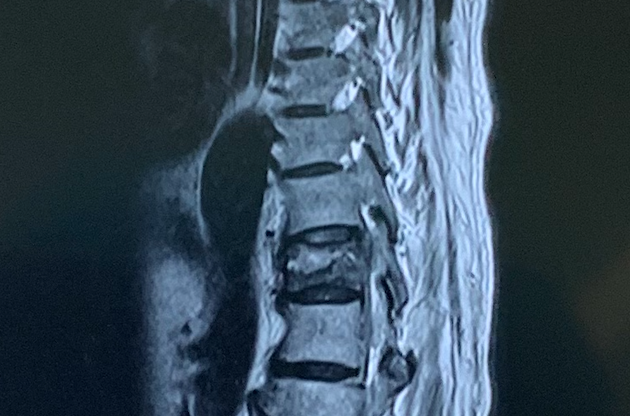

检查发现,在老人的胸椎上有一处骨折,已经存在很长的时间了。由于没有得到很好的治疗,在骨折之后还经常起身站立,身体的重量压在断裂的椎体上,造成骨折不愈合。长期不愈合,骨折椎体骨质吸收,中部形成一个明显的裂隙。身体的重力作用在骨折的部位,裂隙被压缩,造成驼背。在站立的姿势时,身体的压力会造成这个间隙闭合。而在平躺的时候,已经闭合的间隙又在身体的重力下被牵引张开。这会带来很大的痛苦。所以老人一直都惧怕平躺。每天只能在座椅上半靠着,忍受着背部的痛苦。